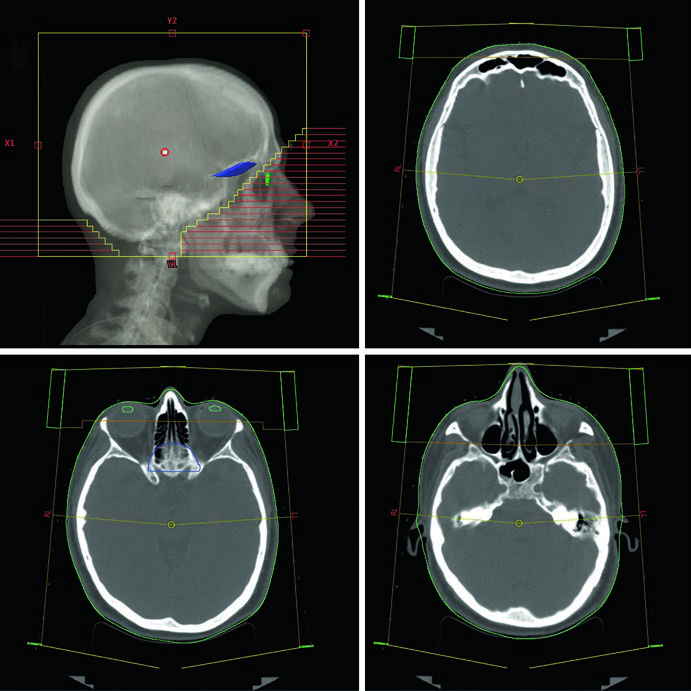

Metástases Cerebrais

Em metástases cerebrais, a página de abertura enquadra a decisão que mais reorganiza o plano: radioterapia de cérebro total ou radiocirurgia estereotáxica. O texto lembra que a escolha depende do número e do volume das metástases, além do performance status, e resume um contraste clínico importante: SRS preserva melhor função neurocognitiva e qualidade de vida, enquanto WBRT melhora controle intracraniano distante e global. Para ver a construção completa do capítulo, leia o artigo detalhado sobre metástases cerebrais.